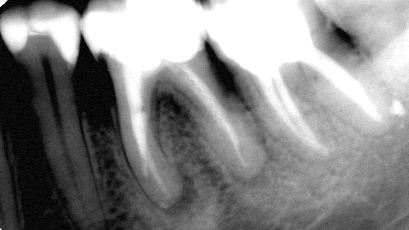

Pacjentka zgłosiła się z bólem. Kilka miesięcy wcześniej leczona kanałowo lewa dolna szóstka. Ząb wrażliwy na nagryzanie. Podjęto decyzję o ponownym przeleczeniu kanałów korzeniowych. Zamknięto perforację przy wejściu do dalszego kanału, usunięto złamaną igłę lentulo z dalszego kanału, udrożniono mezjalne kanały, aż do perforacji korzenia w policzkowym bliższym kanale. Wypełniono dalszy kanał gutaperką, bliższe kanały wypełniono MTA. Ząb do obserwacji, najprawdopodobniej będzie wykonana resekcja wierzchołków bliższego korzenia, na poziomie perforacji.

Reendo 46.